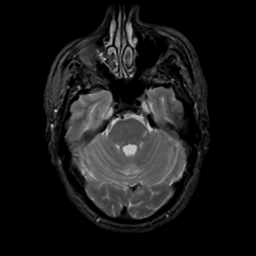

MR Study #1, February 10, 1991 -- Slice #14

[Home][Help][Clinical][Tour 1][Tour 2] Slice 14